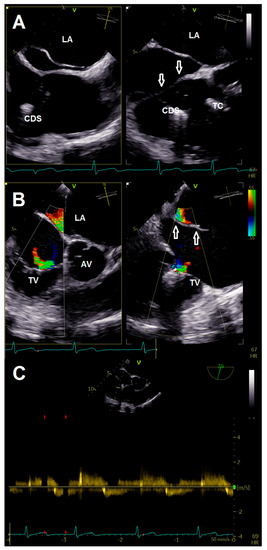

A 78-year-old female patient presented at the emergency department due to progressive dyspnea and a weight gain of 15 kg in recent weeks. Physical examination revealed massive peripheral edema and concomitant congestive dermatitis, but no jugular vein distention. Laboratory results were suggestive for diagnosis of cardiac decompensation with N-terminal pro-brain natriuretic peptide (NT-proBNP) plasma levels of 2320 ng/L, while renal function and inflammation parameters were unremarkable. As the patient was already known to have severe TR with last heart failure hospitalization one year ago, she was admitted for cardiac recompensation and evaluation of tricuspid valve intervention. Further notable medical history included permanent atrial fibrillation, iron deficiency anemia, and severe osteoporosis with previous spondylodesis and extensive oral pain therapy. Echocardiographic examination confirmed progression to massive TR (Vena contracta: 15 mm, effective regurgitation orifice area: 0.9 cm²), but also revealed an additional right atrial membrane ranging from the interatrial septum to the ostium of the IVC consistent with a CTD (Figure 1, Videos S1–S8). Application of contrast medium, as part of the bubble study, yielded an additional patent foramen ovale (PFO, Figure 2A,B; Videos S9 and S10). Besides, both atria (left atrial volume index, 109 mL/m2; right atrial volume index, 189 mL/m2), the right ventricle (right ventricular end diastolic diameter, 51 mm), and the IVC (33 mm) were severely dilated, whereas the left ventricular end diastolic diameter (46 mm) was in normal range. Right ventricular (tricuspid annular plane systolic excursion (TAPSE), 23 mm) and left ventricular function (ejection fraction, 60%) were preserved. Furthermore, liver vein congestion with flow reversal and incipient parenchymal liver disease, interpreted as cardiac cirrhosis, were identified underlining the significance of present TR (Figure 1E). Invasive coronary angiography excluded the presence of coronary artery disease, right-heart catheterization determined an isolated postcapillary hypertension (pulmonary artery pressure, 52/17/29 mmHg; wedge pressure, A-wave—20 mmHg, V-wave—23 mmHg, mean—19 mmHg). Cardiac computed tomography was conducted for the purpose of interventional planning (Figure 2C).

Figure 1. (A) Transthoracic four chamber view displaying the additional membrane in the right atrium (arrows). (B) Transesophageal four-chamber view demonstrating the membrane (arrow) resulting in a cor triatriatum. (C) Multiplane color doppler image revealing massive tricuspid regurgitation. (D) Continuous wave doppler showing no significant tricuspid gradient excluding tricuspid stenosis. (E) Flow reversal in liver veins; (F) 3-D image for visualization of access route. Abbreviations: IVC, inferior vena cava; LA, left atrium; LV, left ventricle; RV, right ventricle; TV, tricuspid valve.